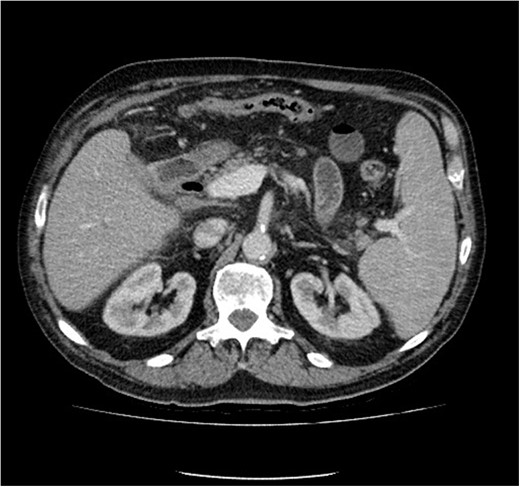

Initial upper GI endoscopy failed to enter the duodenum due to residue within the stomach with the appearance and odour of faeces noted. Abdominal computed tomography (CT) suggested a cavity with adherent ileum adjacent to the second part of the duodenum (Fig. 1). A contrast study was then undertaken demonstrating rapid flow of contrast into the terminal ileum and caecum originating from the duodenum (Fig. 2). Repeat upper GI endoscopy demonstrated an abnormal fungating fistulous communication between the duodenum and terminal ileum which permitted the full insertion of the endoscope (Figs 3 and 4). Biopsies were consistent with diffuse B-cell lymphoma (DLBCL) in accordance with the WHO classification.

Computed tomography image of duodenal-ileal mass (arrow indicates cavity).